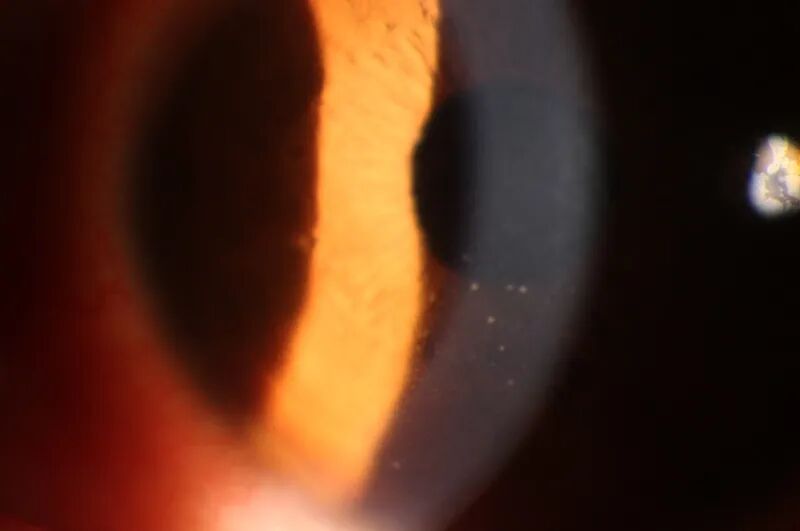

05    角膜变性与营养不良

角膜变性(左)大多数是由于眼部炎症性疾病或某些先期疾病引起的角膜组织退化变质并使功能减退。营养不良(右)是角膜组织受某种异常基因的决定,结构或功能进行性损害并发生具有病理组织学特征的组织改变。